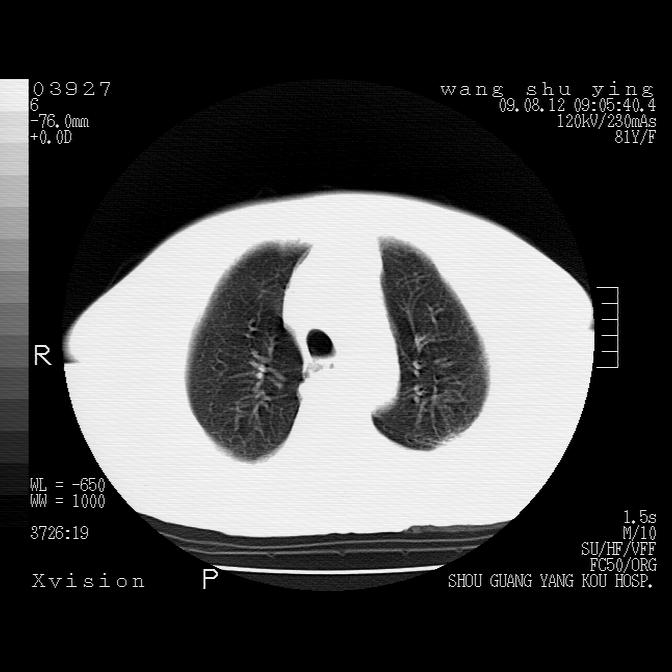

以下是引用帅河马在2009-8-12 12:59:00的发言:[br]两肺感染性病变伴双侧胸膜肥厚。[br]左侧甲状腺腺瘤不除外。[br]腹水+心包积液。[br][br][本贴已被 帅河马 于 2009-8-12 13:14:32 修改过]

以下是引用sdzyy在2009-8-12 18:17:00的发言:[br]两肺感染性病变伴双侧胸膜肥厚。[br]左侧甲状腺腺瘤不除外。[br]腹水+心包积液。[br]支持

以下是引用随光逐影在2009-8-12 19:42:00的发言:[br]1)两肺感染性病变伴双侧胸膜肥厚。2)不排除左侧甲状腺腺瘤。3)肝脏占位性病变;建议行进一步检查。